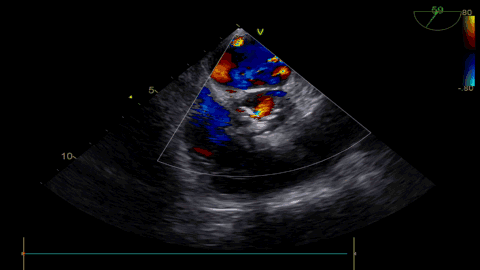

球扩后超声

发生瓣叶切割,无窦侧瓣叶切割,Type0结构形变为类三叶瓣结构。